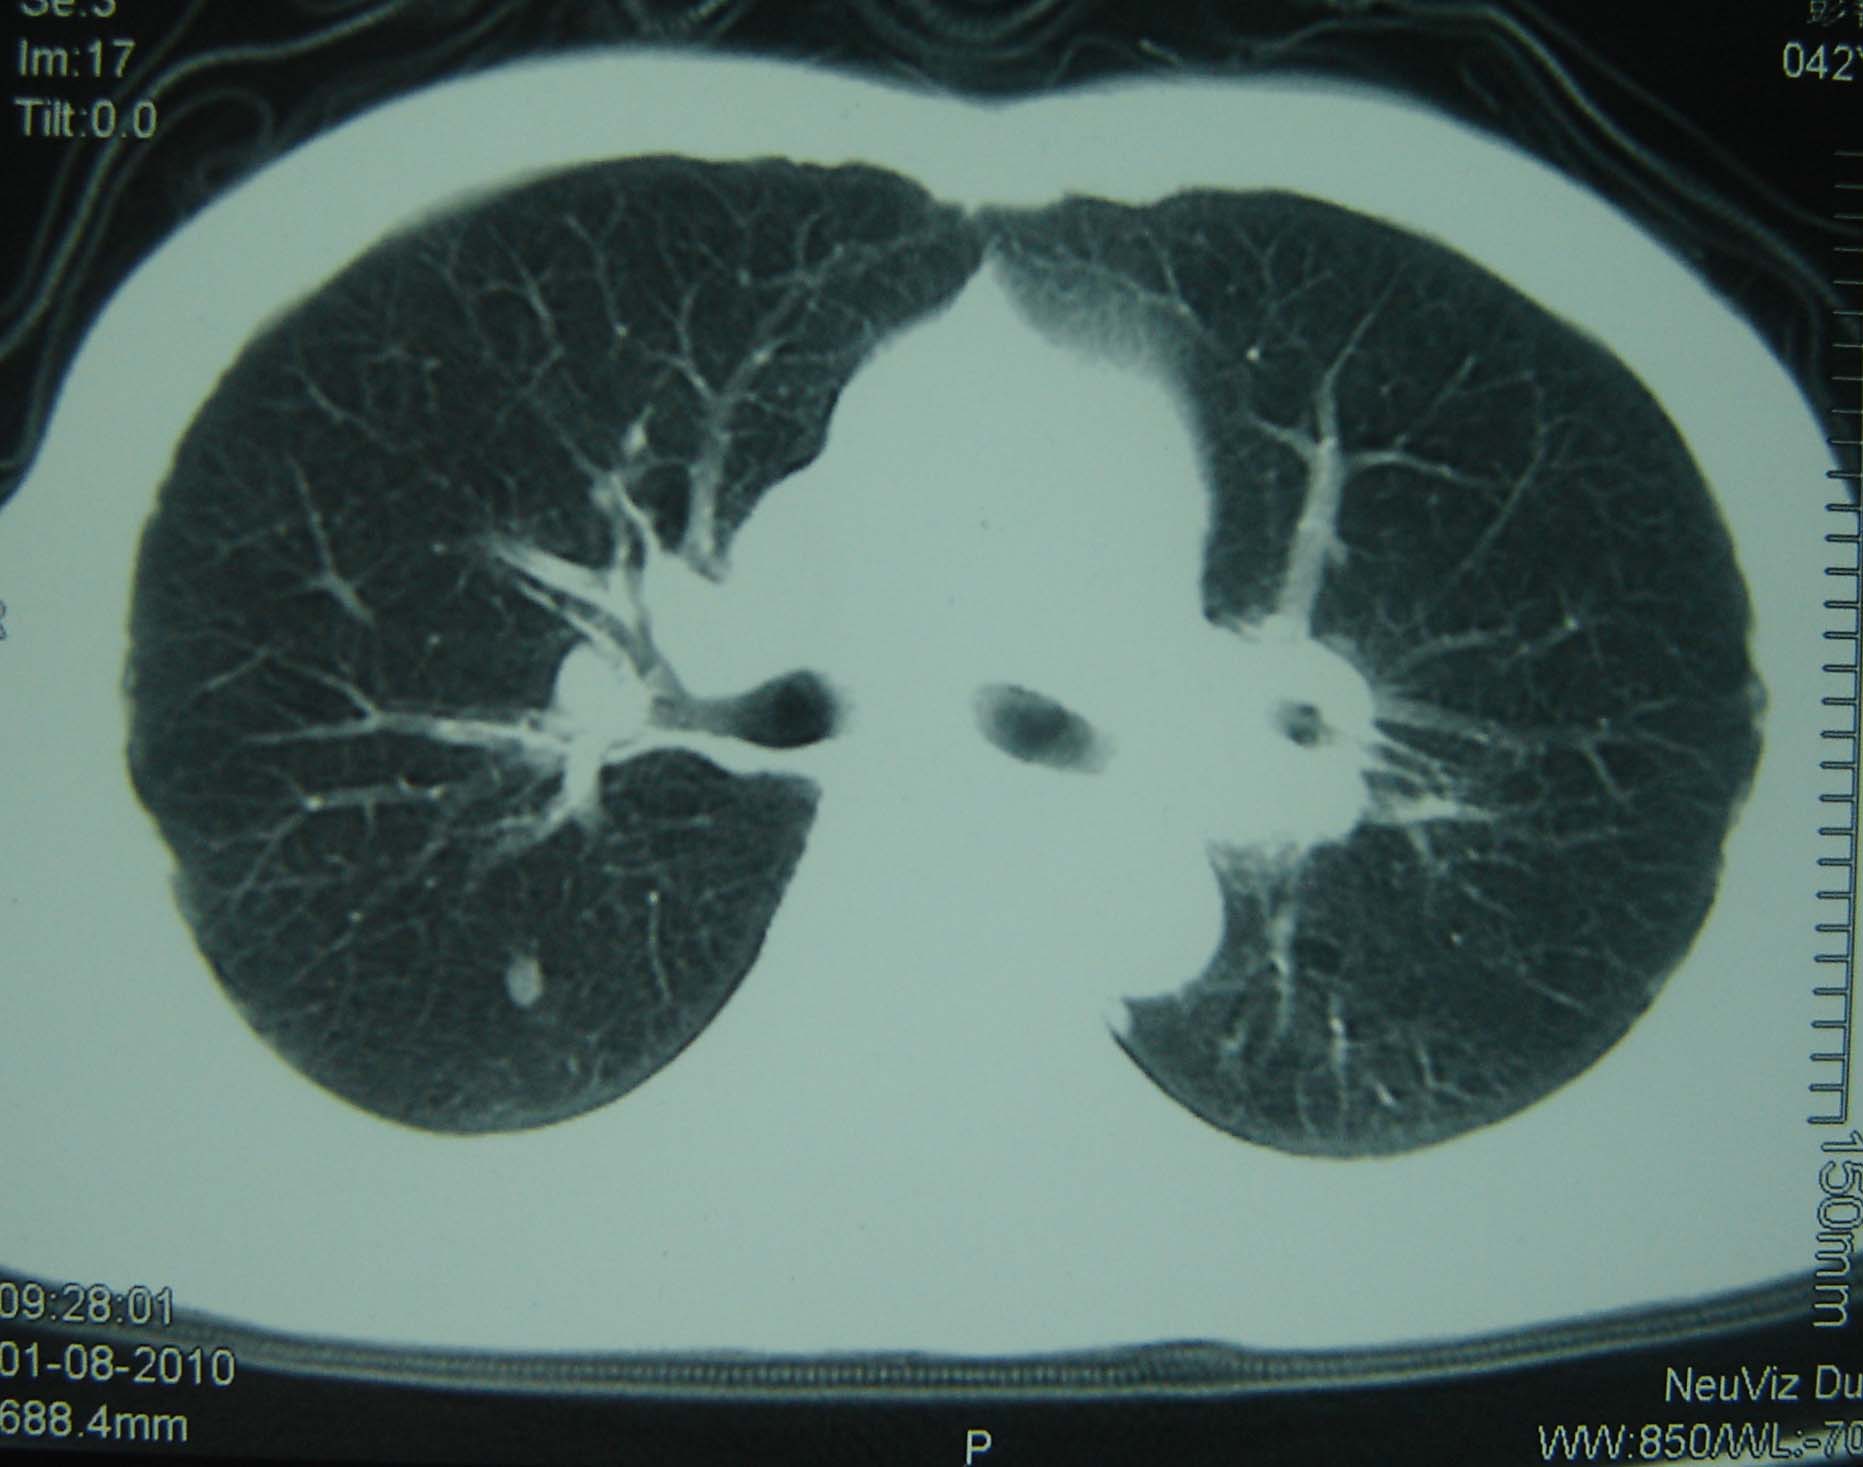

标题: CT25321:两肺多发结节 请会诊 [打印本页]

男 、43岁,咳嗽胸痛,装修工,平时接触粉尘较多,有吸烟史10多年,纤维支气管镜检查未发现异常,胃镜、腹部b超检查亦未发现异常,颈部淋巴结活检未发现肿瘤细胞。

不能排除转移,如果不能找到原发灶,只有短期随访。

结节病?转移瘤?

1)考虑双肺及胸膜多发性转移瘤。2)肺气肿。